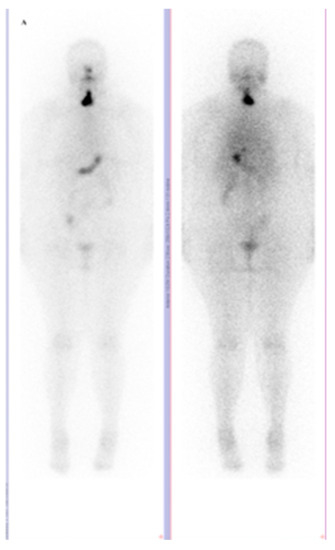

Skeletal Muscle Metastasis in Papillary Thyroid Microcarcinoma Evaluated by F18-FDG PET/CT